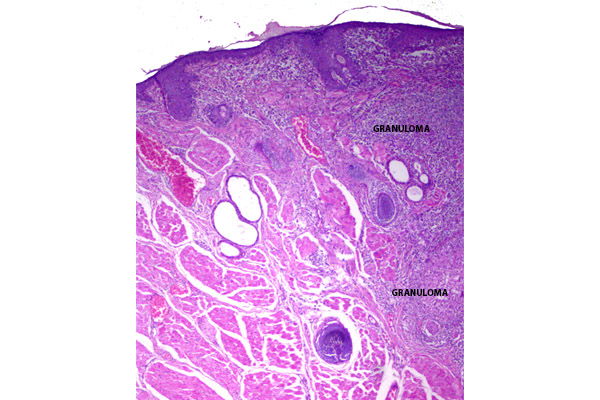

En un corte histológico del párpado se aprecia un granuloma compuesto principalmente por células epitelioides y células gigantes.

Los granulomas se distribuyen difusamente, alterando la histología del párpado.

Presencia de granulomas en la dermis superficial y profunda.